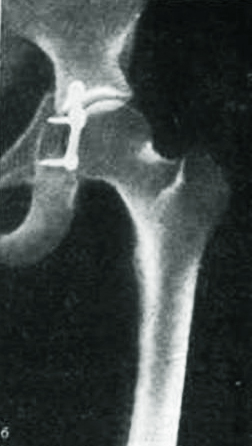

На сегодняшний день золотым стандартом при лечении переломов тазобедренного сустава является операция остеосинтеза, позволяющая быстро зафиксировать костные отломки и максимально восстановить функционирование тазобедренного сустава. Оперативное лечение проводится по медицинским показаниям.